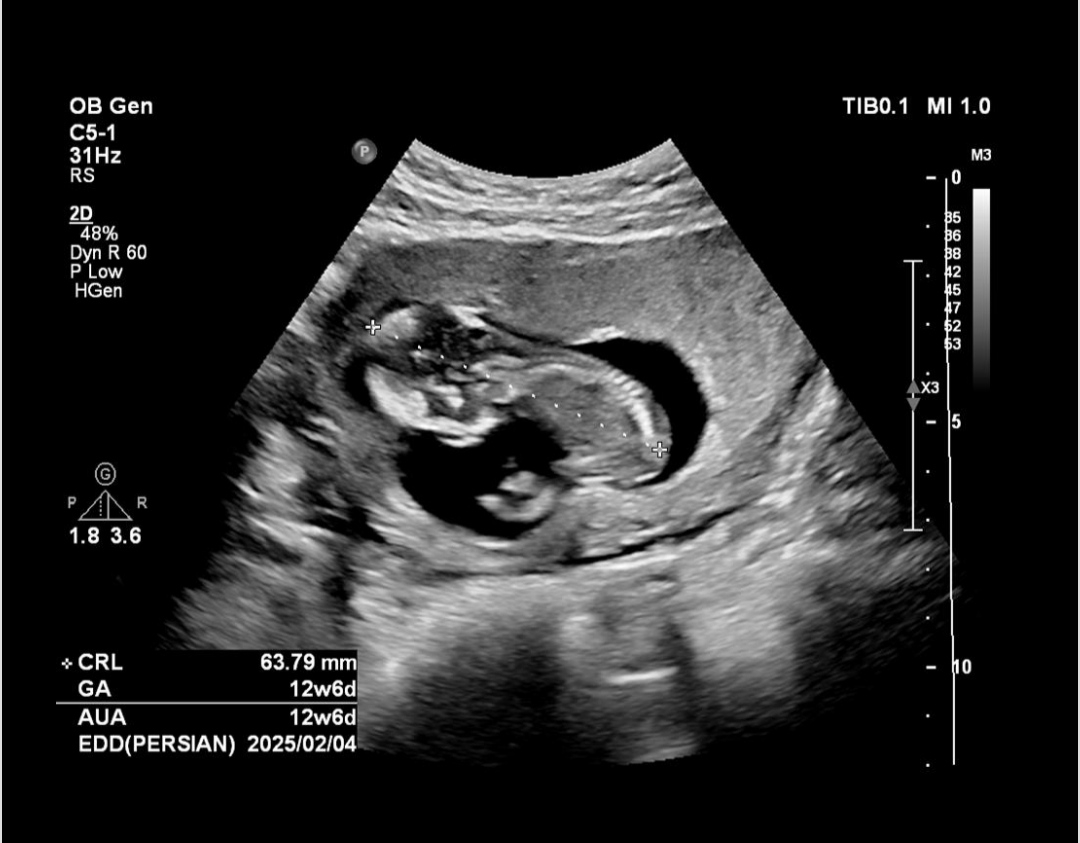

من دیشب رفتم سونوگرافی و بعدش آزمایش.. داخل سونوگرافی وقتی دکتر داشت سونو میکرد به دستیارش گفت nb دیلیت(یعنی چی!؟ کسی میدونه!)

من اصلا حواسم نبود و یادم رفته بود nb چیه تا الان یهو یادم اومد رفتم برگه سونو نکاه کردم دیدم چیزی درباره nb ننوشته. راستش نگران شدم جواب آزمایش هم گفته دو هفته دیگه آماده میشه

عکس سونو الان میزارم ببینید

اینم عکسا بچه

درمورد nb در طی سال های اخیر کلا در سیستم نوین گزارش دهی nb از سونوگرافی سه ماهه اول حذف شده در آنومالی گزارش میگردد و برای همین گفته اند nb را وارد گزارش نکنید